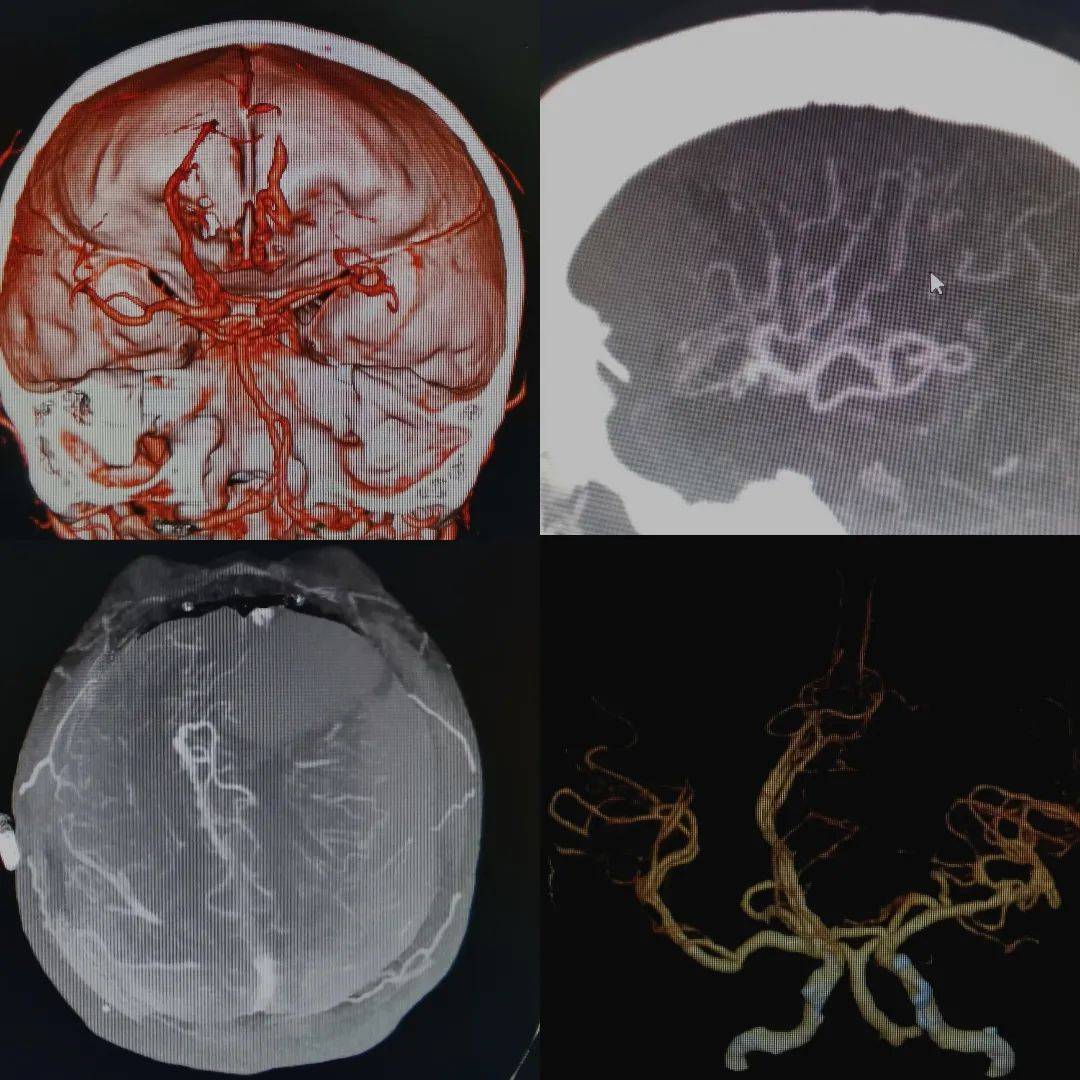

【高尚病例】头颅cta发现脑动静脉畸形1例【成都高尚医学】_手术_血管

仔细阅片cta未见明显引流静脉,考虑右侧脑膜中动脉假性动脉瘤可能更大